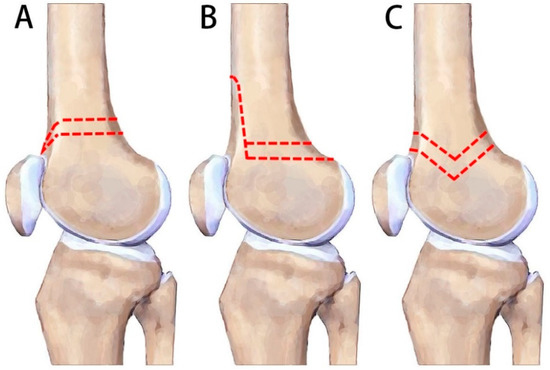

:1. Introduction

2.2. Surgical Technique